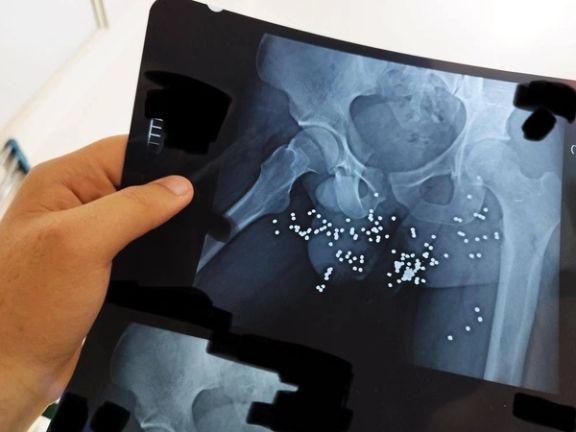

In addition to photos and videos of the injuries, the batch includes dozens of x-ray images and CT scans of pellets and slugs in the head, neck, chest and legs of the protestors. The Islamic Republic has killed many protesters with rubber bullets and metal pellets and blinded so many others.

The regime’s security forces have been extensively using cartridges of shotshell loaded with numerous small balls or birdshots, or medium-sized buckshots as well as single large solid projectiles known as a slug to quash the nationwide protests, ignited by the death in custody of 22-year-old Mahsa Amini in September 2022.

It did not provide names, dates or locations for the photos, which mainly are from injuries that protesters sustained from shotgun pellets as well as bruises and fractures caused after being beaten by the security forces. Most of the photos and videos are so graphic that cannot be republished by Iran International.